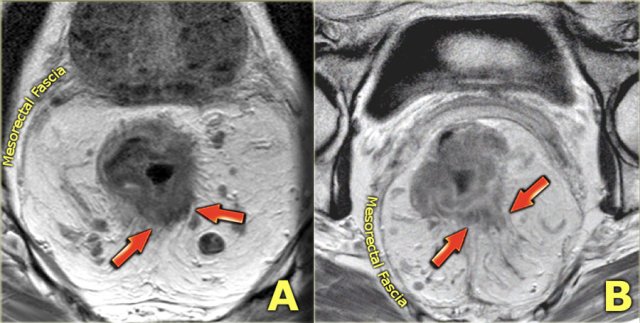

It can be difficult to discern true perirectal tumor invasion in T3 tumors (case A) from desmoplastic stranding in T1-2 tumors (case B), which can be a potential cause of overstaging.

Note:

The clinical significance

to discern T2 from borderline T3 tumors has been argued as various current guidelines – including the Dutch guidelines –

classify T3 tumors with limited extension into the mesorectal fat (cT3ab) in

the same good prognostic group as T2 tumors for treatment stratification.

In some guidelines, however, T3 disease by itself is still considered a factor used to determine the need for neoadjuvant treatment.